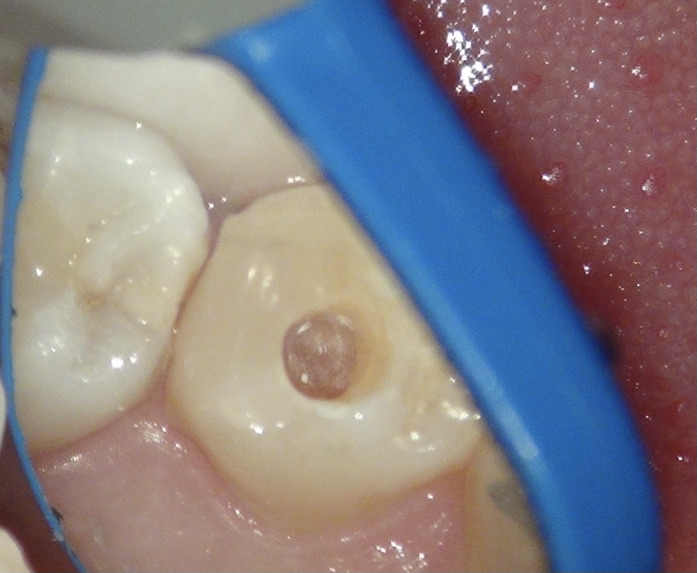

お口の中を拝見し、レントゲンを撮影。

口腔内を見た状態 キレイにレジンが詰められていますね

上の写真は舌側(内側)からみたところ